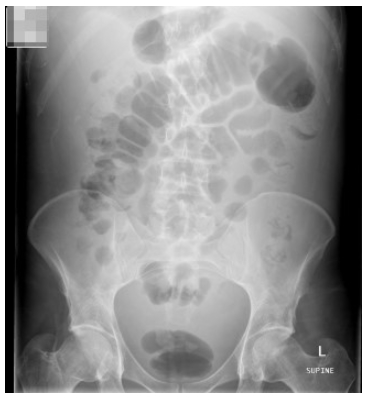

원인에 관계 없이 복수가 있으면 전형적으로 신체 진찰에서 옆구리 탁음(flank dullness)이 있습니다. 이동 탁음(shifting dullness, a change in the location of dullness to percussion when the patient is turned due to movement of the ascites) 또한 있을 수 있습니다. 복수가 있는 경우 복부 엑스레이에서 bowel은 중앙에 위치해 있습니다.